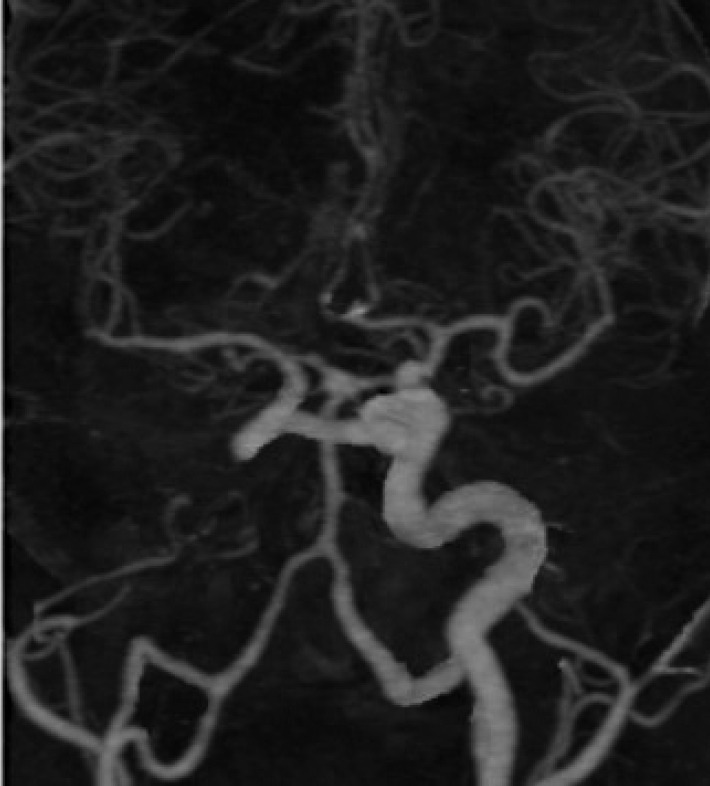

Developmental anomalies of internal carotid artery (ICA), being rare entities, are mostly asymptomatic by themselves because of good collateral supply. However, when present with other associated intracranial anomalies requiring treatment, there can be catastrophic consequences, if special attention is not paid to this condition. We present a case of 36 years old male, who reported to our emergency department with complaints of headache and loss of consciousness. He was diagnosed as a case of ruptured anterior communicating aneurysm with subarachnoid hemorrhage and agenesis of left ICA with trans-cavernous anastomosis. He underwent clipping of aneurysm and was discharged uneventfully. This report highlights the importance of skillful microsurgical clipping in extremely high-risk conditions, in contemporary era of hybrid neurosurgeons.